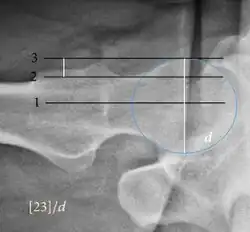

| Femoral head-neck offset | ![]() |

Offset of the femoral head with regard to most prominent aspect of the femora neck | >10 mm |

| Offset percentage | Femoral head-neck offset related to femoral head diameter | >0.18

| |